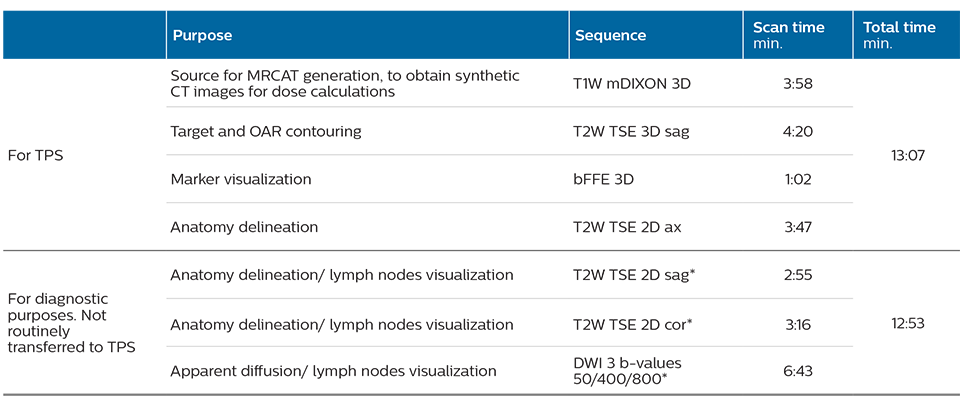

The TYKS MRI examination for generating the images for prostate MR-only simulation includes the standard sequences for MRCAT (Magnetic Resonance for Calculating Attenuation) generation, contouring and fiducial marker visualization. The total scan time for the RT planning sequences is 13 minutes. The ExamCard is customized with additional T2-weighted and DWI sequences for diagnostic purposes which makes total scanning time 26 minutes. The patients are imaged on a flat RT tabletop, using an Anterior MRI coil that is placed on a coil holder to avoid deforming body contours.

The MR images needed for RT planning are exported to the treatment planning system (TPS), where the MRCAT images are handled as a CT image set by the TPS, with no manual postprocessing required. Target and OAR delineation is performed using the T2-weighted images.

TYKS MR-only examination